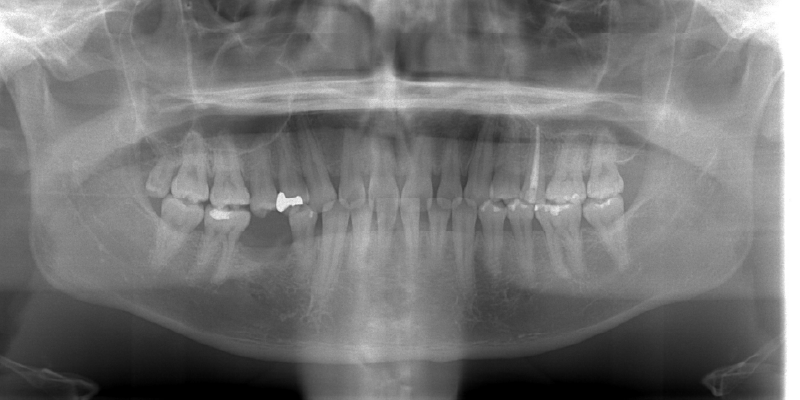

天然歯のような噛み心地

インプラントは、顎の骨にしっかりと固定されるため、まるで自分の歯のような自然な噛み心地を再現できます。入れ歯のようなズレや異物感がなく、硬いものも安心して噛むことが可能です。日常の食事や会話を快適に楽しめる、それがインプラントの大きな魅力です。